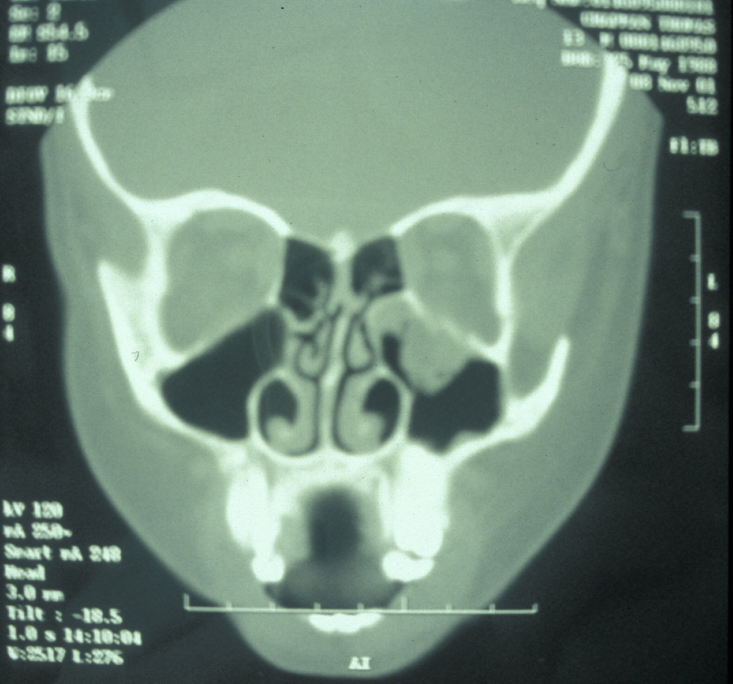

Plain film X-ray radiographs from different angles generally give sufficient diagnostic information. Combined they give good imaging of the zygomatic complex and can be used to determine the level of displacement and fracture pattern. Teardrop appearance into the maxillary antrum suggests an isolated orbital floor fracture (a 'blow out orbital fracture'; see Figure 8). Identification of this type of fracture mandates further investigation by a coronal (vertical plane view) CT scan and Hess chart test (eye test to assess motility of the eye).

Figure 8: A coronal CT scan showing a ‘blow-out’ fracture of the orbital floor.